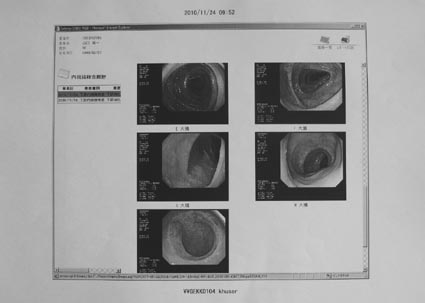

2)CT検査・下部内視鏡

<所見> 異常なし